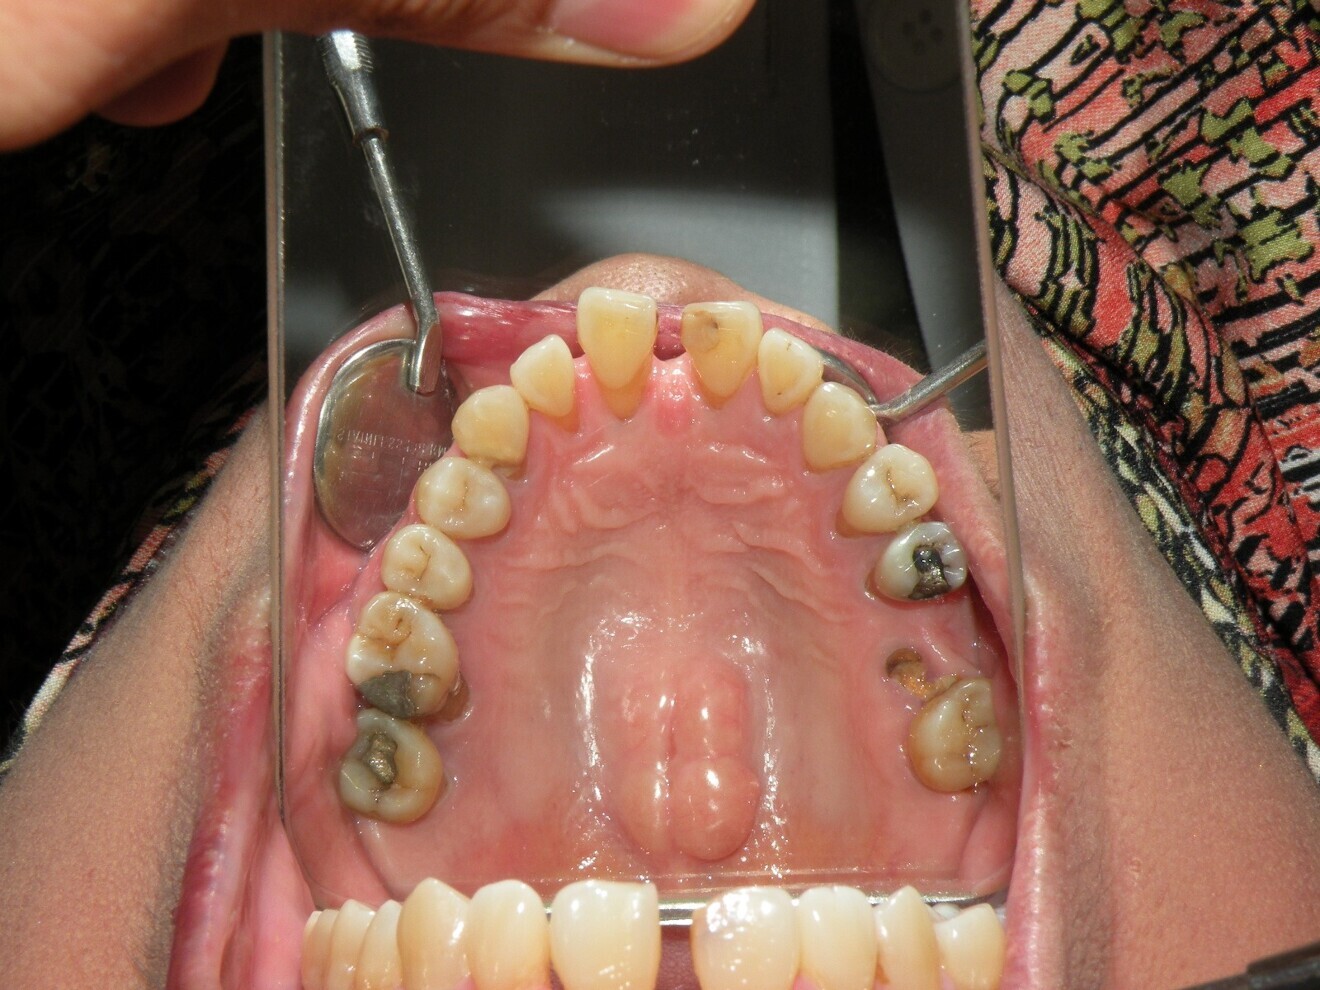

Intra-oral findings:

Class I malocclusion with poli diastemas in the upper anterior region.

Overbite= 2mm, Overjet= 2mm.

No molar classification (absence of molars).

Class I canine on right and left side.

Upper midline (mesial to 11) on with face.

Lower midline on with the chin.

Panoramic radiograph analysis:

Missing 17, 26, 38, 36, 46 and 47.

Retained root 16, 45.

Poor prognosis 26.

Increased vertical bone loss especially 11,21 (only ~30% left)